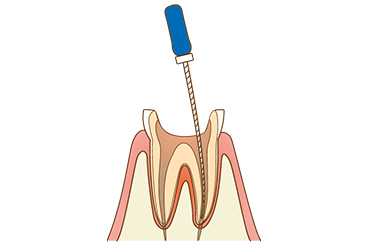

【3】根管の拡大

根管内に薬剤を詰めやすくするために、根管を削って拡大します。

【4】根の清掃・消毒

x徹底的に根の部分を洗浄・消毒することで虫歯菌を完全に除去し、再発を防ぎます。